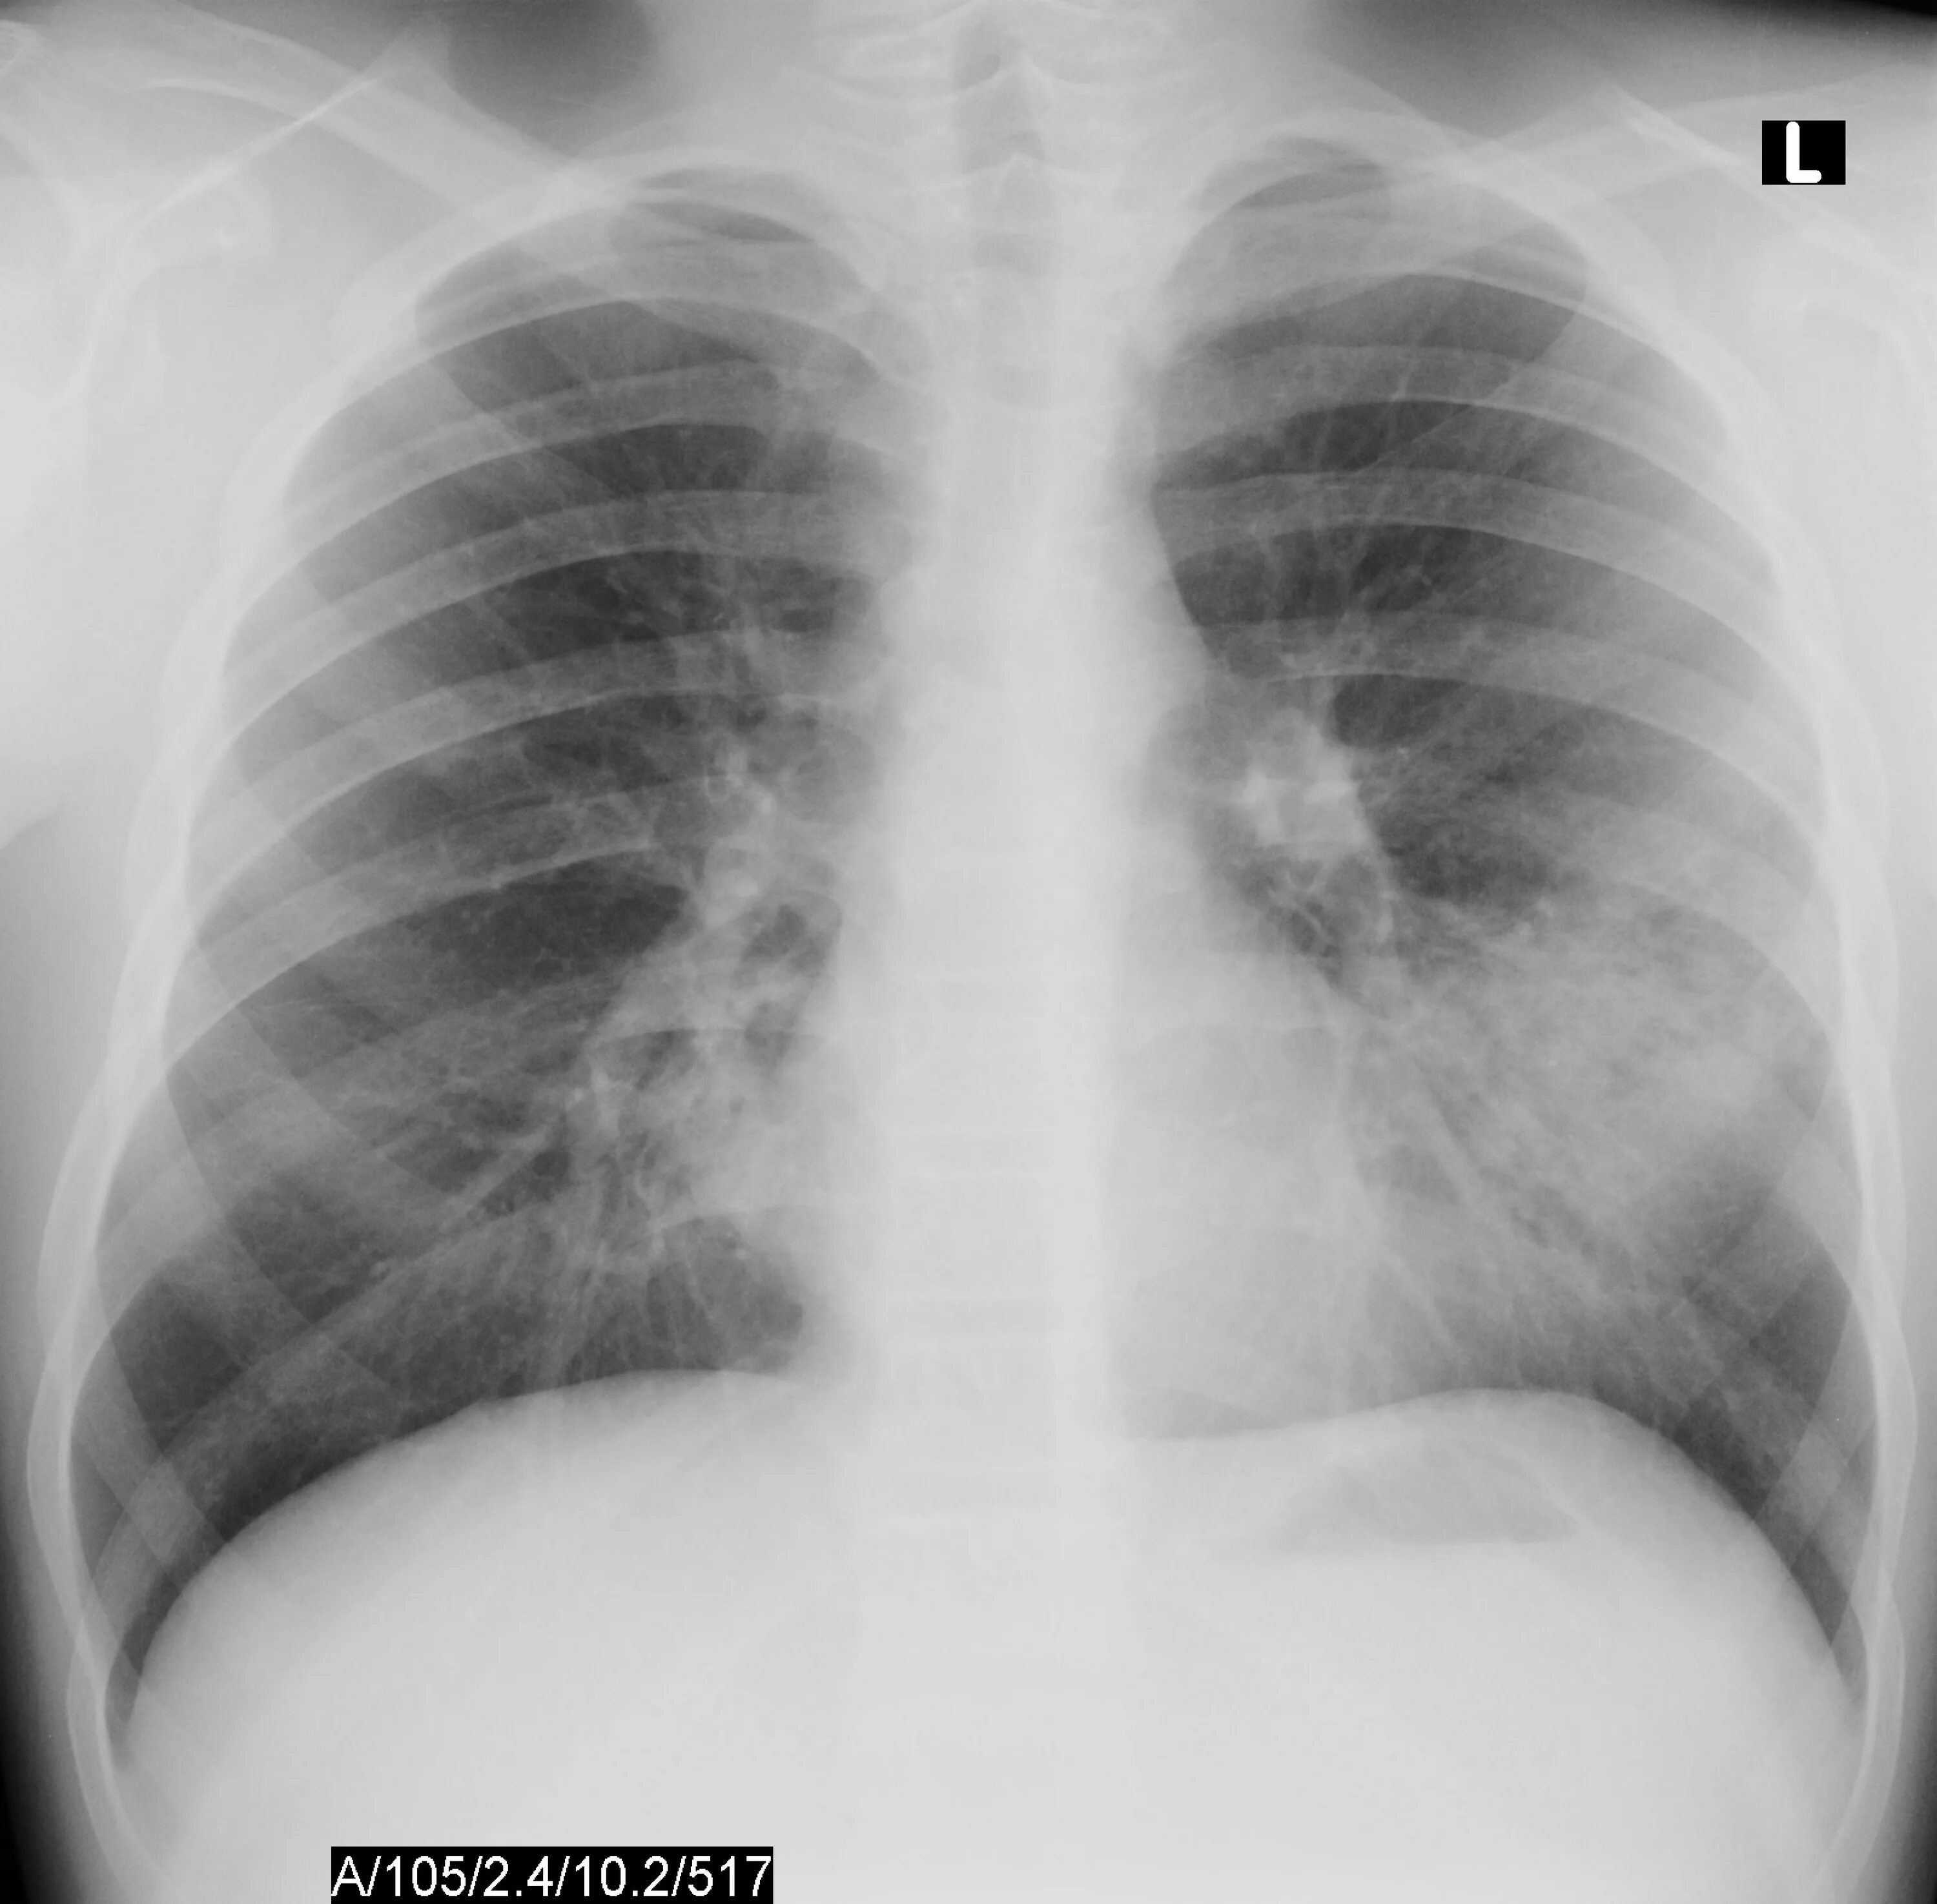

Атипичная пневмония у взрослых